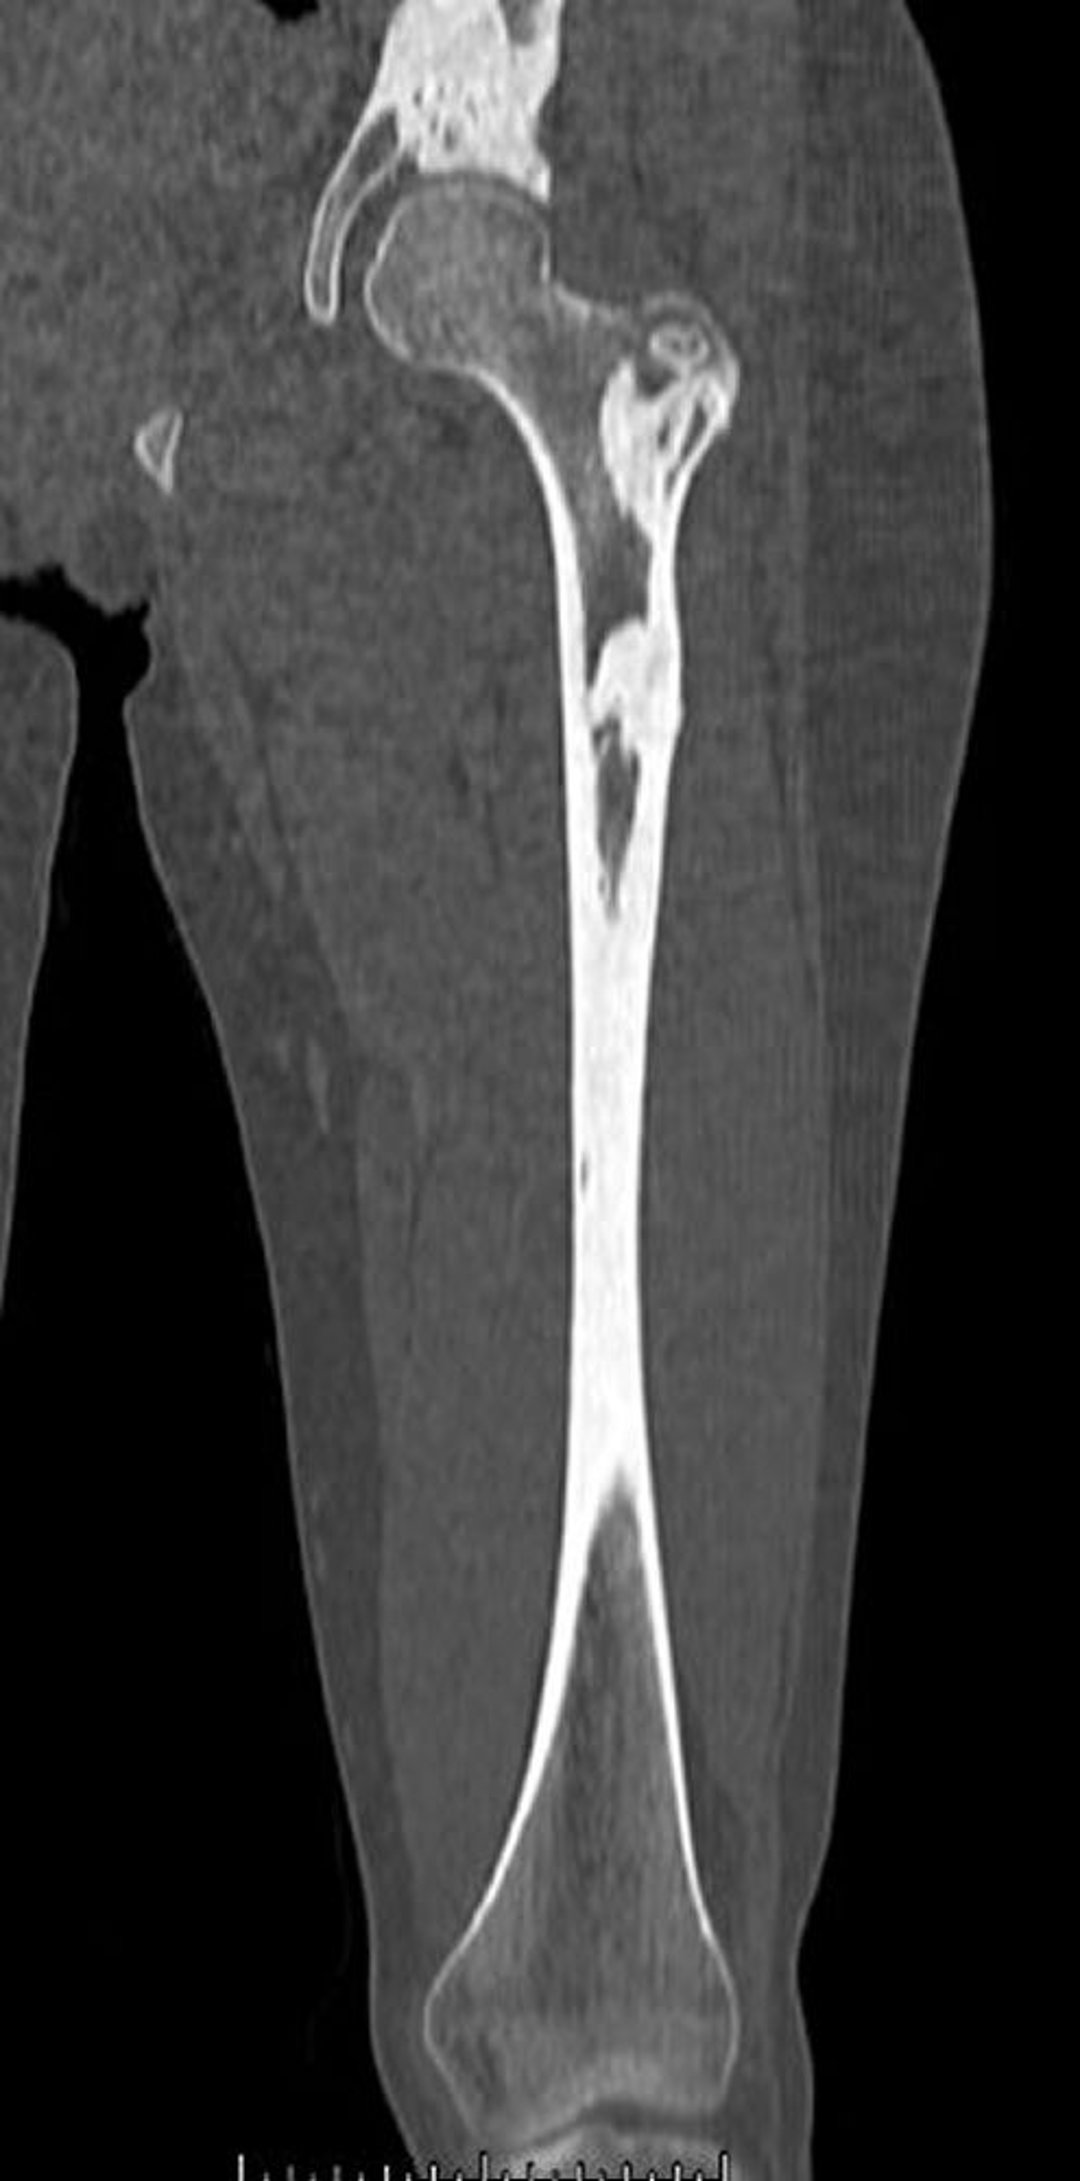

Melorheostose (CT)

Diese CT-Aufnahme zeigt die dichten Knochenläsionen der Melorheostose im Femur und im Becken.

Image courtesy of Michael J. Joyce, MD, and David M. Joyce, MD.